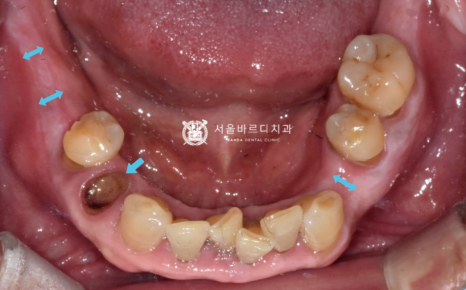

그래서 환자분과 오랜 상의 끝에

오른쪽 위아래 뿌리만 남은 자리를 뽑고,

왼쪽 위에는 이가 없는 동안 솟구쳐 내려온

치아를 뽑은 후에 임플란트를 진행하기로 했습니다.

20230130

임플란트의 뿌리 역할을 하는

픽스처를 넣기 위해서 충분한 폭이 필요한데

이를 뽑은지 오래되어 치조골의 폭이

많이 좁아져 있었습니다.